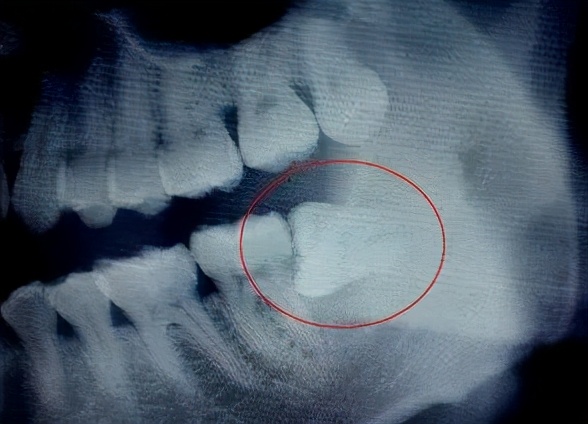

05 智齿影响

我周围很多朋友,包括我自己都有长智齿,可 千万别小瞧智齿 了。

有的智齿“不听话”,位置长得不好,变成 水平阻生牙 ,在它生长的时候产生的力量会压迫邻牙向前移动, 导致其他的牙齿空间被挤压 。这就是为什么有的人原本有一口整整齐齐的牙齿,长智齿就变得有点歪了。